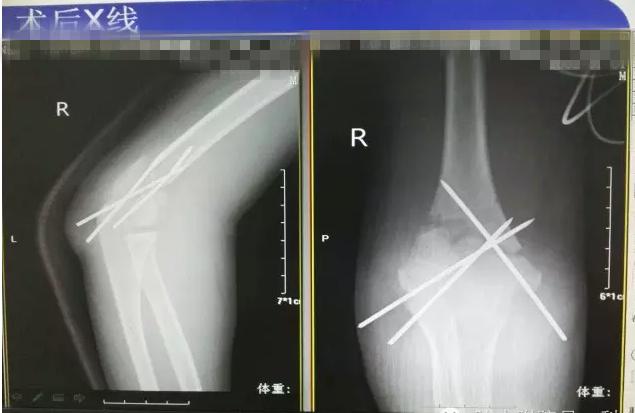

病案二:患儿谭XX,男,14岁,摔伤后右肘关节疼痛伴活动受限5小时入院。

诊断:Gartland III型骨折

术后长臂石膏维持屈肘中立位固定